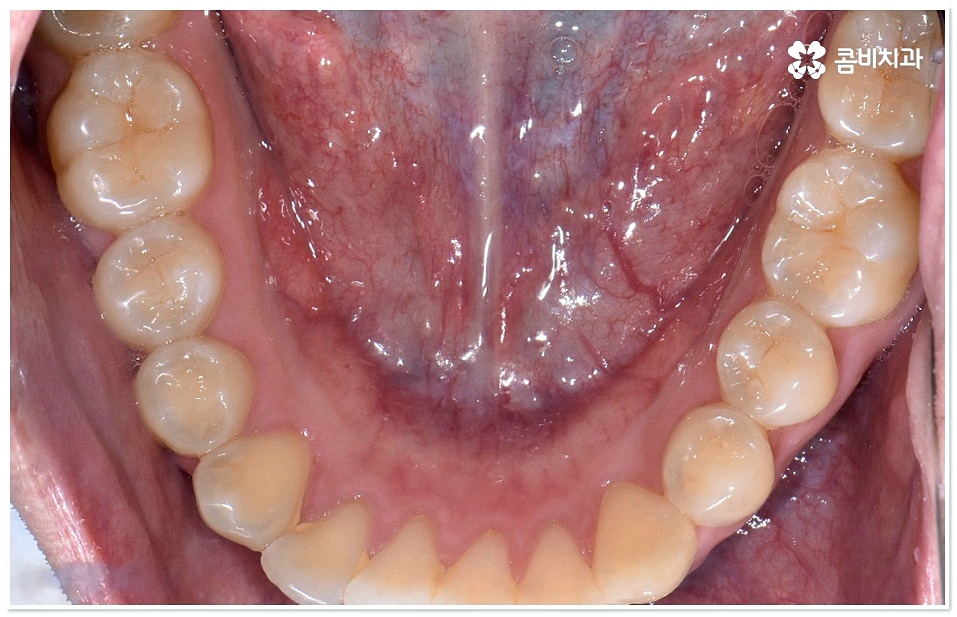

교정 치료란 특수한 장치를 이용해 치아를 원하는 방향으로 이동시켜 치아 배열과 교합을 올바르게 개선해 주는 과정으로 각자의 구강 구조가 다 다르기 때문에 정밀 검사를 통해 환자분들 각각의 치아 모양과 각도, 위치, 교합 뿐 아니라 잇몸 건강 상태 및 상악과 하악의 관계와 같은 구강 내 상황과 함께 입술, 전체 안모 등 대칭과 균형의 측면에서 모든 부분을 다각적이고 입체적으로 분석한 후 세밀한 맞춤 계획을 수립하는 것이 중요할 수 있는데요.

그러므로 3D CT와 같은 정밀 검진 장비와 3D 모르페우스와 같은 시스템을 갖추고 다양한 경험과 노하우를 바탕으로 정확한 진단 및 섬세한 플랜을 세울 수 있는 치과를 잘 알아보고 덧니치아교정 치료를 진행하실 필요가 있어요.